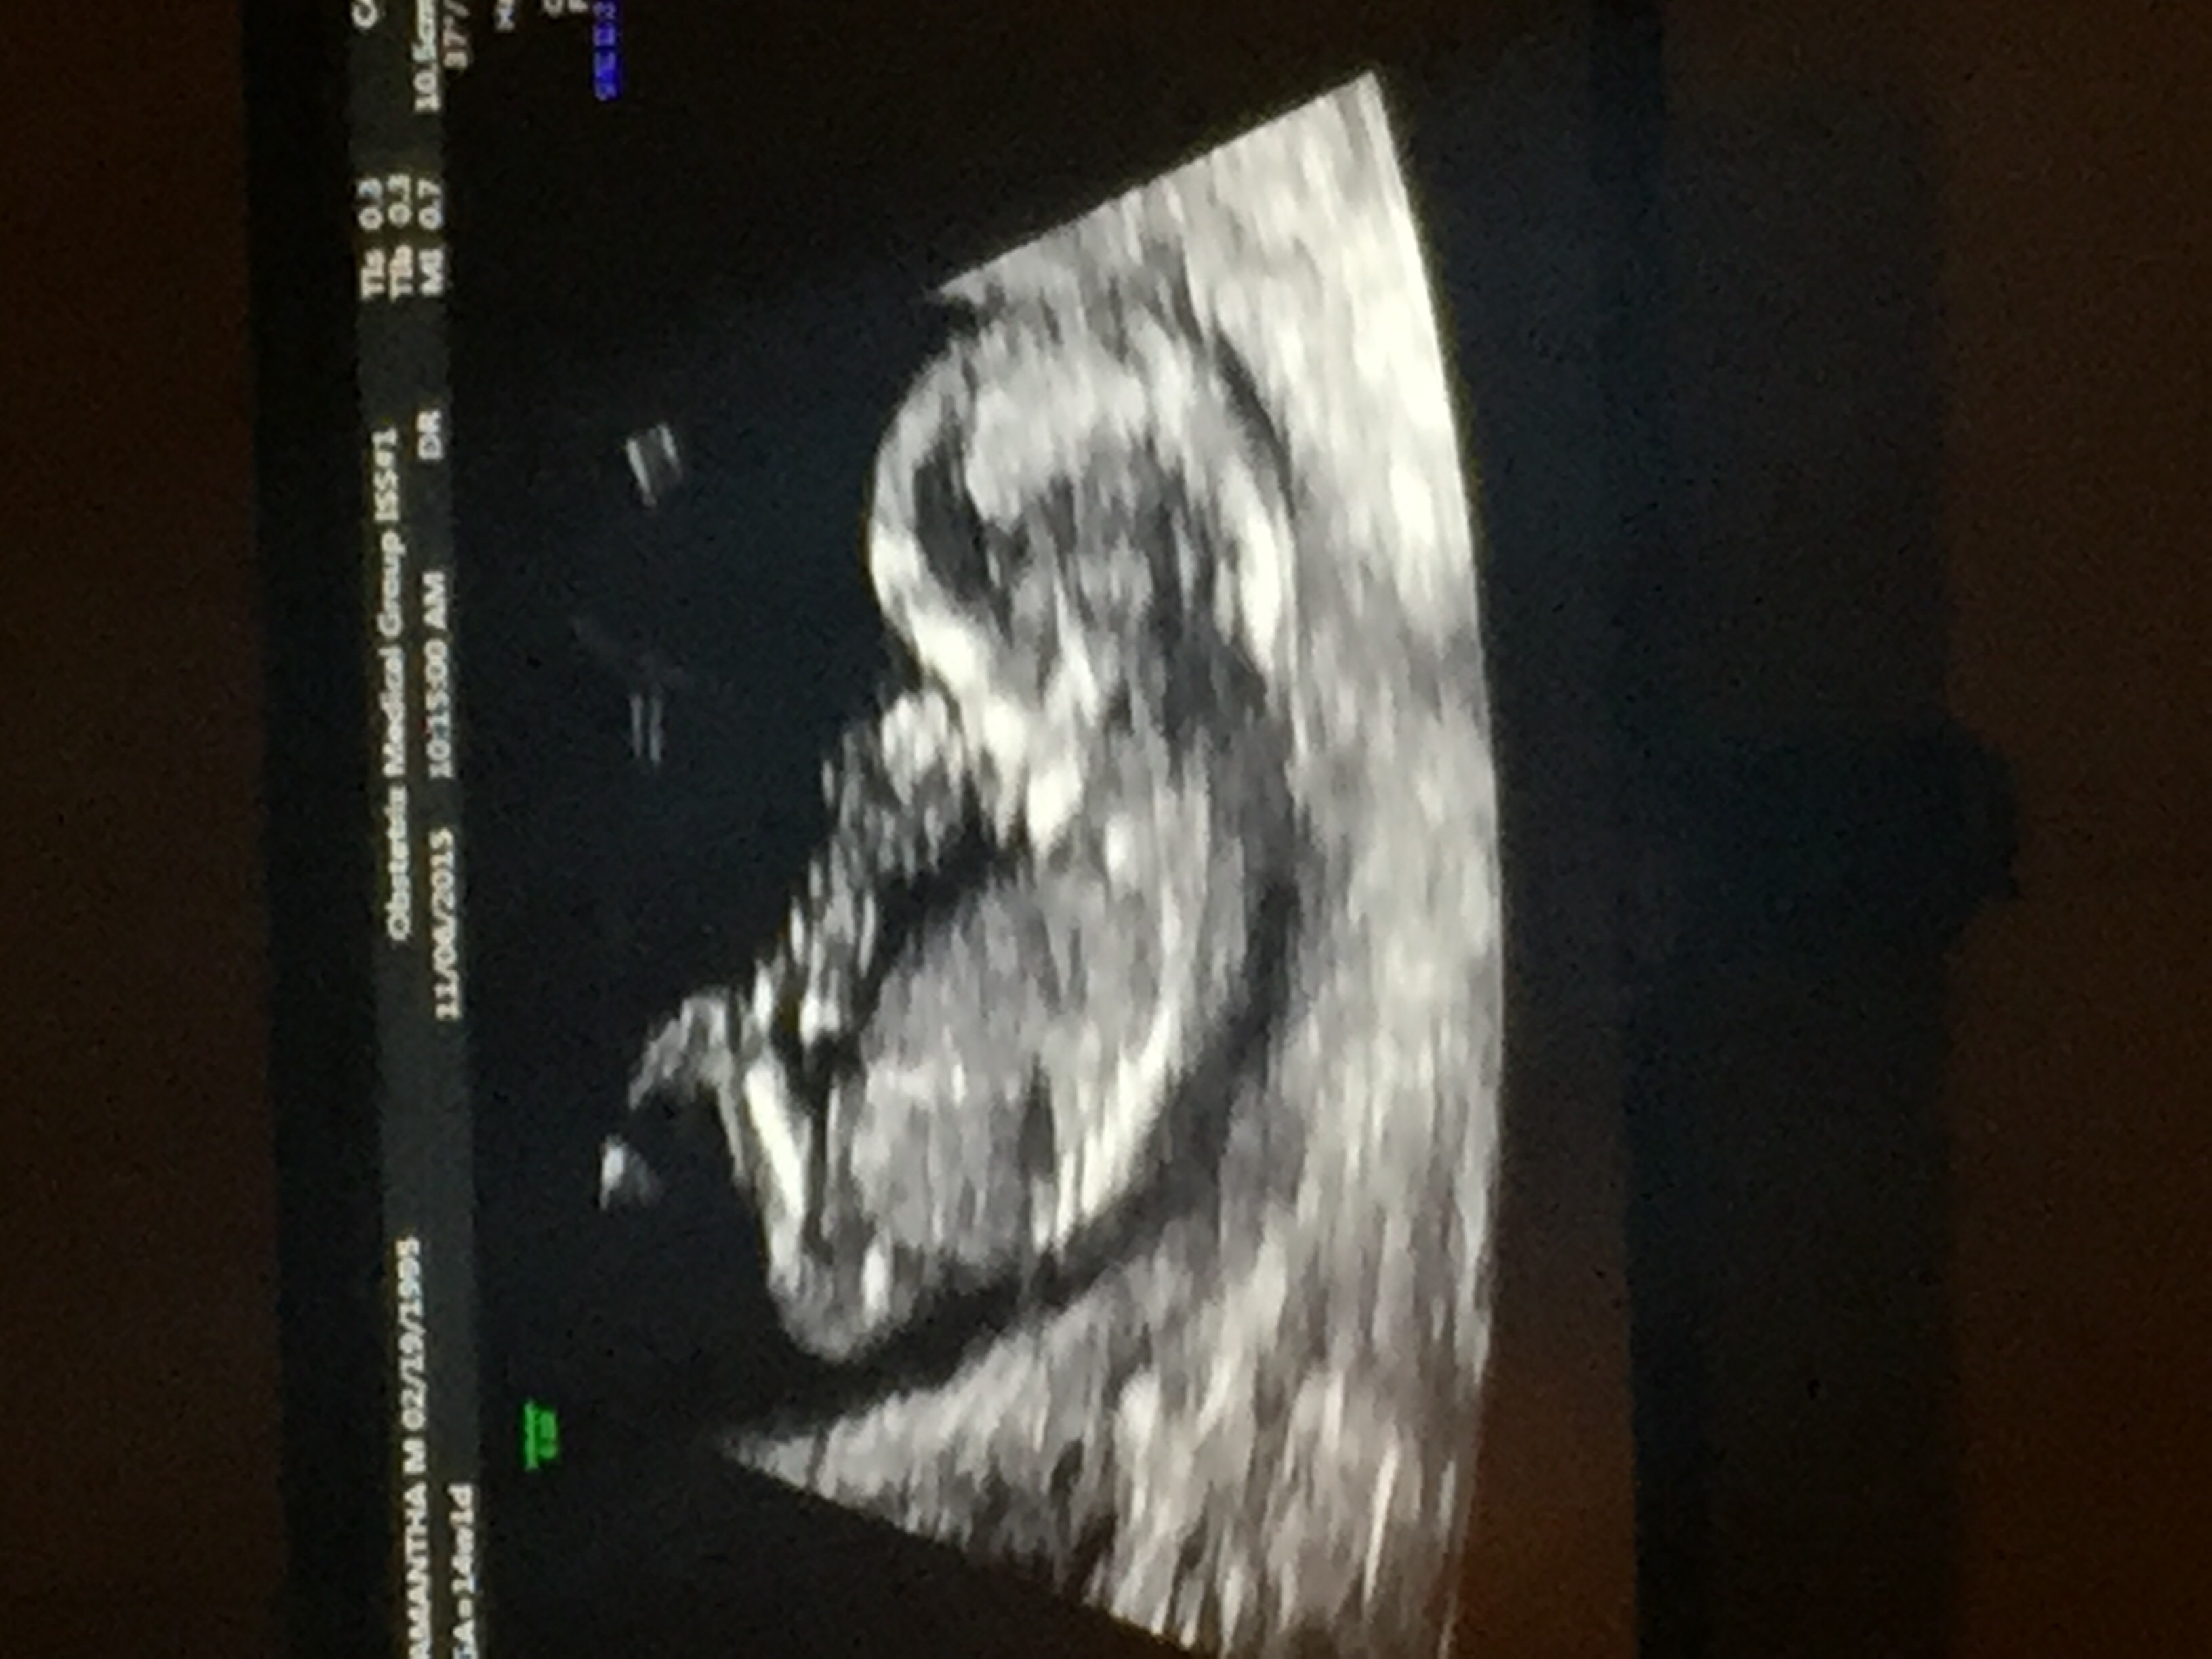

I have had 2 previous ultrasounds already, but my anxiety is really high with this one due to previous losses I called my Dr today. Luckily, my Dr does his own ultrasounds so I don't have to wait for the ultrasound techs, and he was able to get me in this afternoon just to take a look and ease my anxiety. Baby is great, heartbeat is strong and I was able to see baby wiggle a little! Thank goodness my Dr understands and was able to fit me in today! My anxiety dropped so much!

This was our first ultrasound at 12 weeks 4 days! It has been the best day of my life thus far. It was so exciting and the baby moved constantly!! We get to find out the gender on November 24! So that is our next exciting thing to look forward to!!!

Had my NT scan yesterday. Everything looked great! This baby has been extremely active during each ultrasound. The baby was opening it's mouth, bringing it's hand to its mouth, kicking its legs, rolled over to the side than again so the butt was in the air. Would not stop moving, definitely put on a show for my husband and I. We loved it!

Got to see baby for the first time yesterday!! Baby was so active!! Me and the family loved it. Based on my last cycle I was suppose to be 14 weeks and 1 day, but baby was measuring 12 weeks and 4 days. My mom mentioned she has always ovulated late, so makes sense. Was beyond happy to finally be able to see my baby ❤️

It felt like foreverrrrrr waiting till 12 weeks for our first ultrasound, but what an amazing sight! Here's baby at 12 wks 1 day. Right on schedule He/She was a pain in the butt for the technician haha wouldn't stay still! I must say, I feel so much more at ease now!